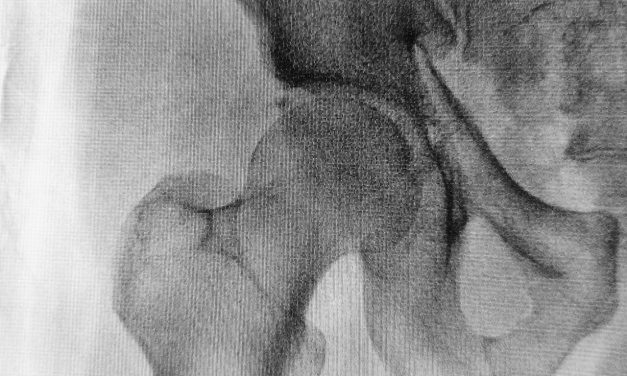

Jak leczy się uszkodzone panewki?

Panewka stawowa jest to struktura kostna, pokryta z zewnątrz tkanką chrzęstną. We wklęsłej...

Czytaj więcejPanewka stawowa jest to struktura kostna, pokryta z zewnątrz tkanką chrzęstną. We wklęsłej...